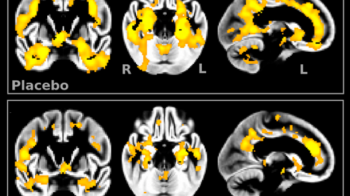

After two years, the rate at which their brains had shrunk was measured.

The team, from the Oxford Project to investigate Memory and Ageing (Optima), found that on average, in those taking vitamin supplements, brain shrinkage slowed by 30%.

In some cases it slowed by more than 50%, making their brain atrophy no worse than that of people without cognitive impairment.